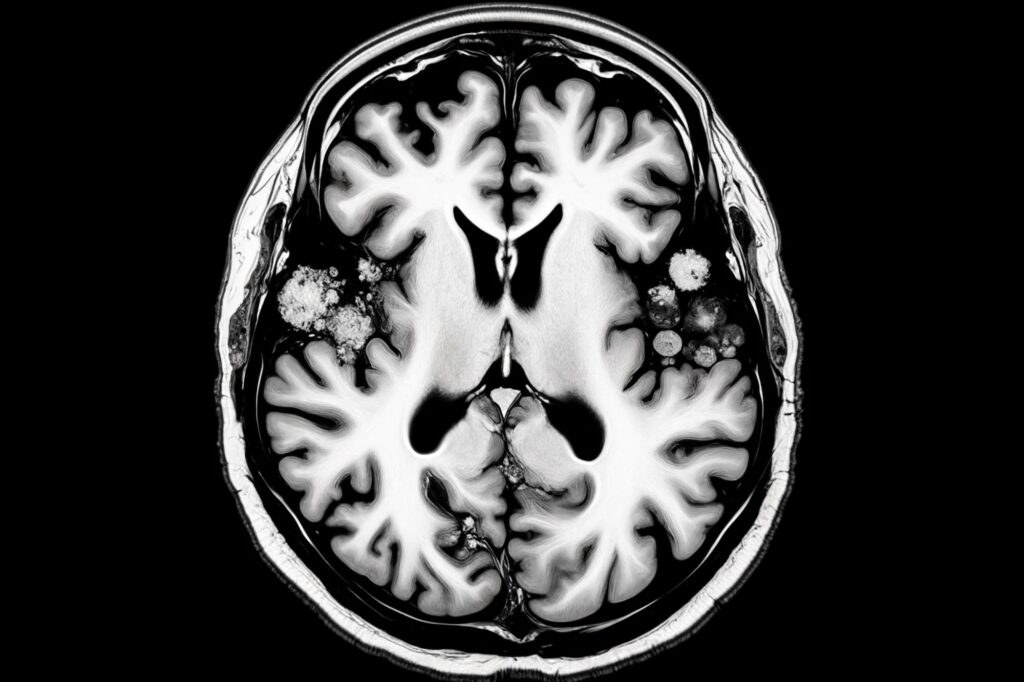

בעקבות אפיזודה של דלקת מוחית חמורה משאיפת פנטניל, אדם החלים בהצלחה בעזרת צוות רב-תחומי ב-OHSU, כמפורט ב- דיווחי מקרה של BMJ. מקרה זה משמש אזהרה לגבי השפעת האופיואידים על החברה. (קונספט האמן.) קרדיט: twoday.co.il.com מקרה מבחן מדגיש סכנה נוספת של פנטניל אסור, במיוחד למשתמשים בפעם הראשונה. האיש הגיע מחוסר הכרה ...